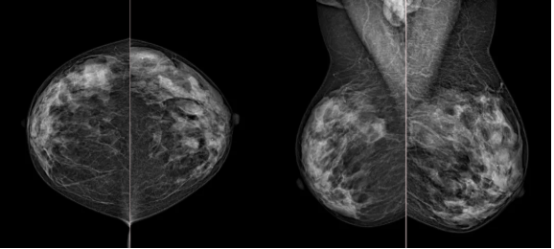

定期做乳腺X线摄影(乳腺钼靶)是早期发现乳腺癌的好方法。公共卫生部门建议定期筛查,特别是有家族史或其他风险因素的女性,以提高早期诊断的几率。

图为乳腺钼靶检测